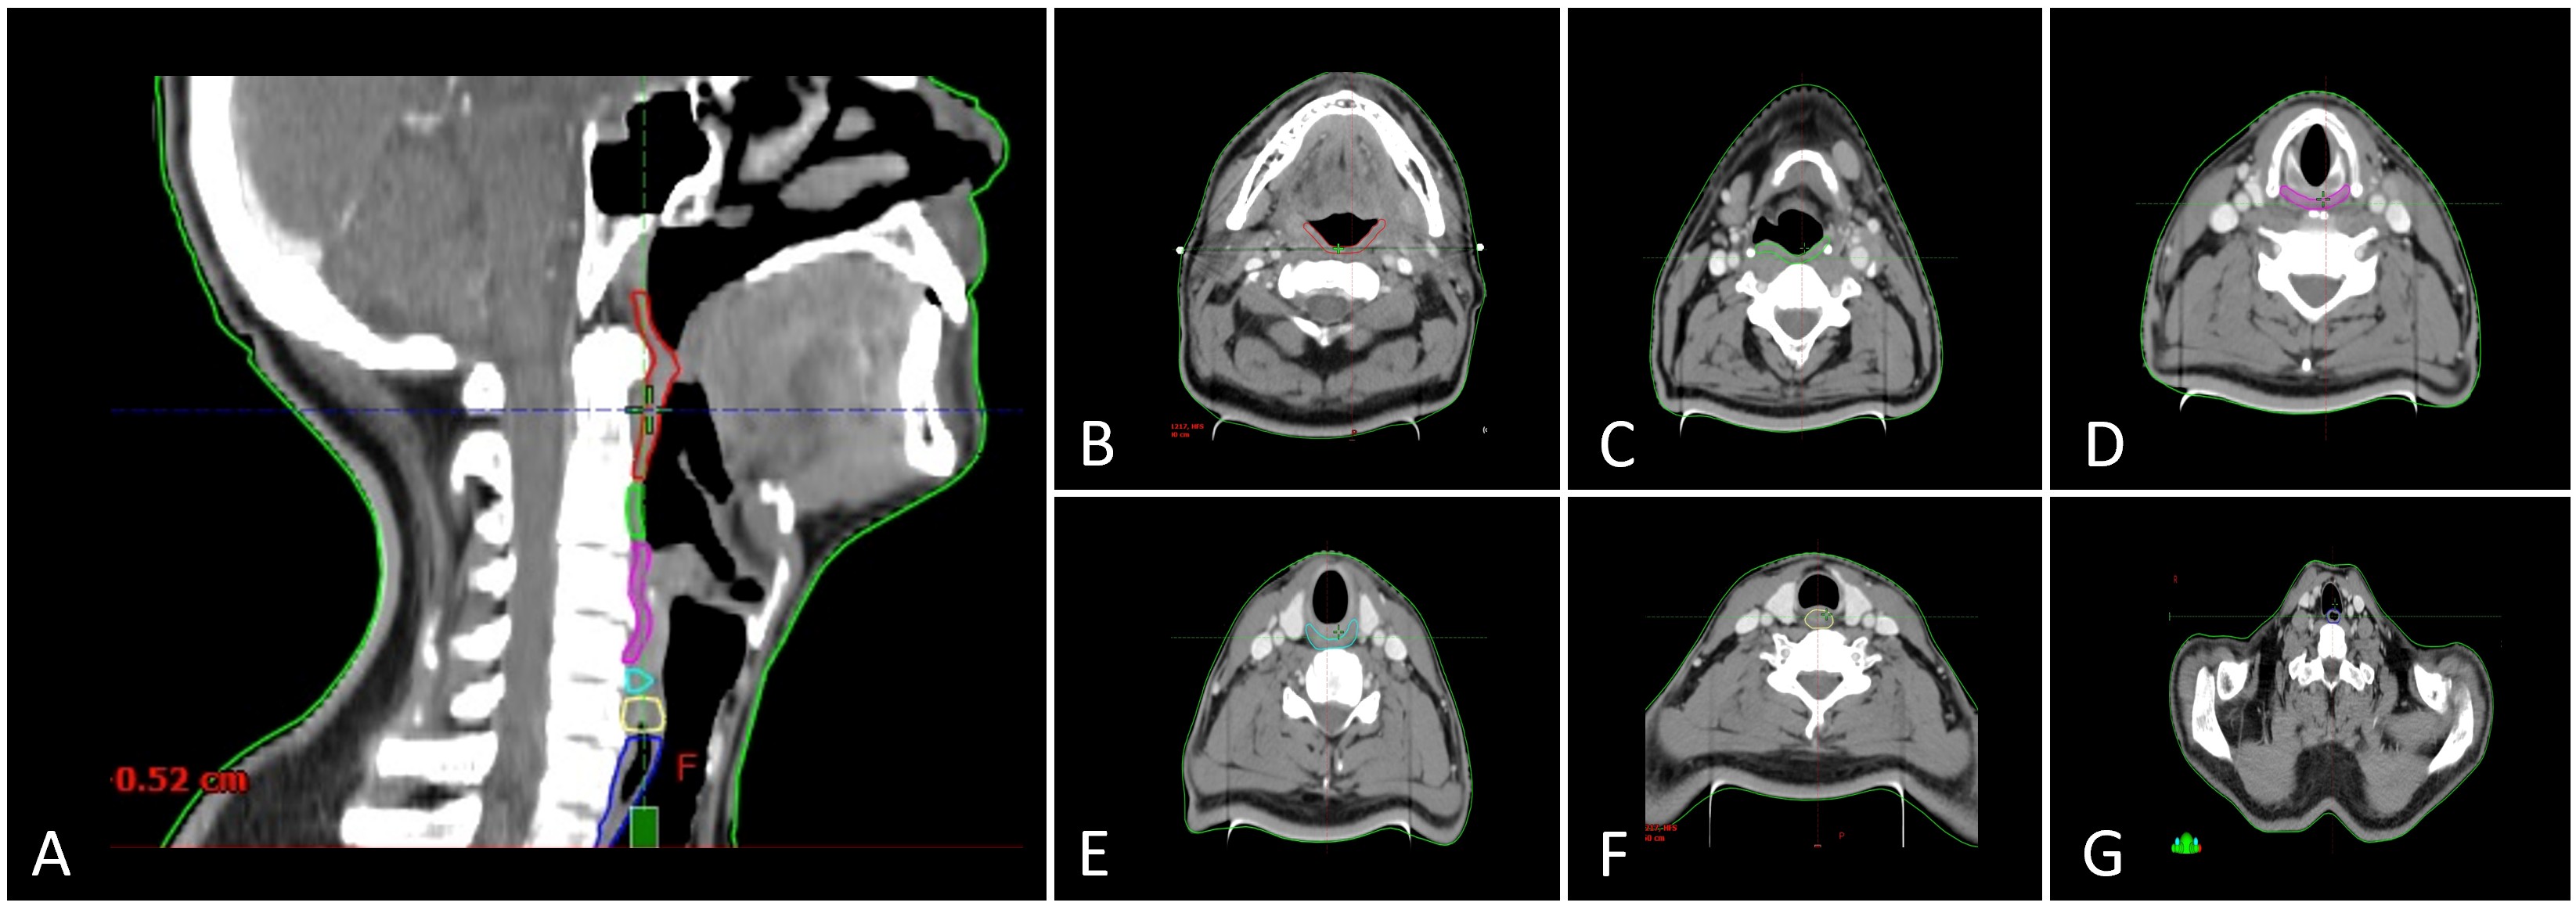

- スワローイング障害の発症を予防・軽減するため、治療計画時に以下を検討:

- スワローイング構造を明確に輪郭付け(delineation)する。

- それら構造への線量を可能な限り低く設定(例えばMean Doseを目標値以下にする等)。

- 頭頸部がん治療では、腫瘍制御のためにどうしても高線量域を設定せざるを得ないケースが多いですが、同時に スワローイング関連構造(PC M、喉頭、輪状咽頭筋など) を OAR として意識し、可能な範囲で線量低減を図ることが重要です。

- 「この構造にはできるだけ Mean Dose を○○Gy以下に抑える」、あるいは「Vx(例 V60Gy)を○%以下に」など、治療施設・プロトコルごとに線量目安を設けることが有用です(ただし汎用的な“安全しきい値”はまだ確立途上です)。